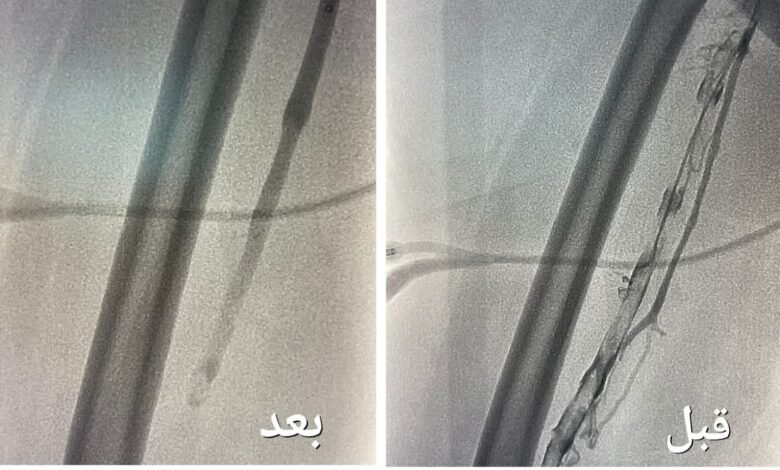

تمكن فريق وحدة الأشعة التداخلية بمجمع الملك عبدالله بجدة من إنهاء معاناة حاجّة هندية تبلغ من العمر ٦٧ عاماً و كانت الحاجّة تعاني من جلطة وريدية من مستوى الكاحل لمستوى أوردة الحوض الأيمن و انتفاخ كامل بالقدم مع عدم القدرة على المشي وأوضحت الصحة أنه بعد إجراء الفحوصات الطبية و الكشف تبين وجود جلطة وريدية من مستوى الكاحل إلى مستوى أوردة الحوض الأيمن و انسداد كامل بأوردة القدم اليمنى حتى الحوض قرر بعدها الفريق الطبي تنويم المريضة و التنسيق مع فريق وحدة الأشعة التداخلية بشكل عاجل لدراسة الحالة و معالجتها و وضع الخطة العلاجية لنقلها لغرف عمليات الأشعة لإجراء عملية بإستخدام جهاز إزالة الجلطات تحت التخدير الموضعي و التهدئة الواعية

وقالت الوزارة إن العملية استغرقت نحو ساعتين تكللت ولله الحمد بالنجاح تم فيها تركيب فلتر للوريد الأجوف السفلي لمنع انتقال الجلطات للرئة و من ثم الدخول للوريد المتجلط بمستوى الكاحل و حقن مواد مذيبة للجلطات و قد أستخدمت اجهزة نوعيه لمثل هذه الحالات والتي تعمل على سحب الجلطات بعد إذابتها و توسعة الأوردة بالبالون لإعادة جريان الدم وأضافت بعد إستقرار حالتها الصحية والاطمئنان و عودة القدم لحالتها الطبيعية و قد بدأت الحركة و المشي و هي الان تتمتع بصحة جيدة ولله الحمد